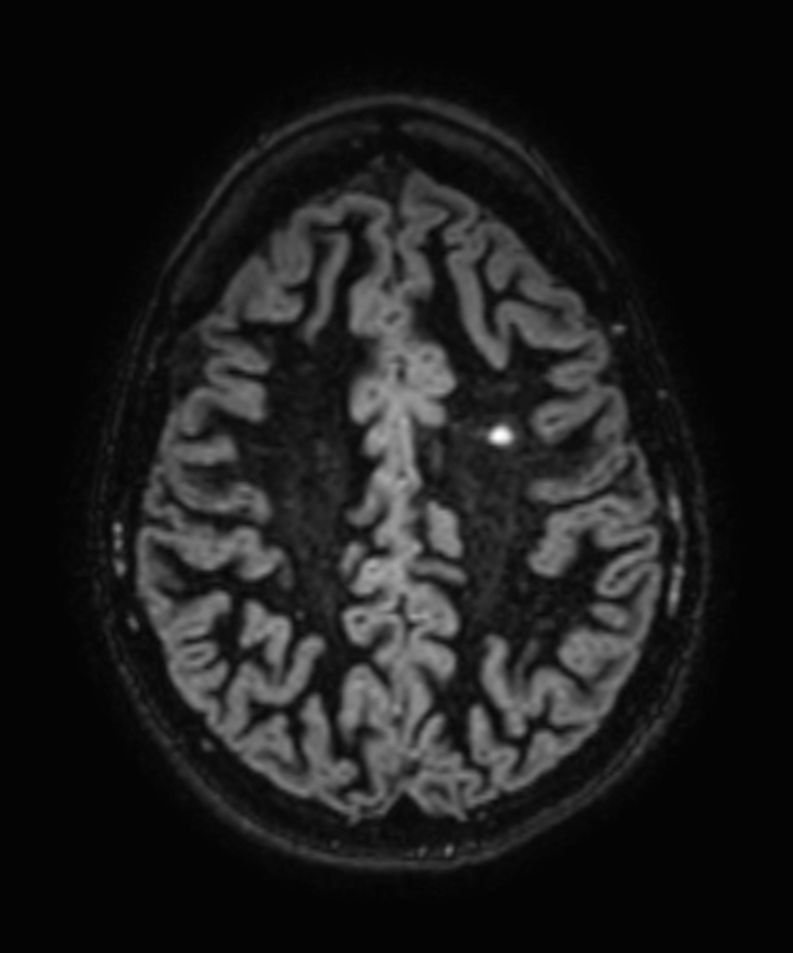

SWI sequence has a high sensitivity to enhance contrast for deoxygenated (venous) blood or calcium deposits. This may help, when used in combination with other clinical information, in the diagnosis of various neurological pathologies. 3D imaging lets you acquire high resolution data in multiple directions in one scan. Isotropic voxel size enables reformats in any plane without loss of resolution. FLAIR* requires offline post processing combining the contrast of 3D FLAIR and 3D SWI EPI into a single image. This enables the visualization of Central Vein Sign, mapping subcortical veins onto 3D FLAIR contrast images.